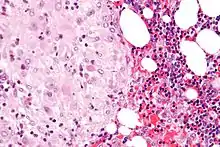

Acute choriodeciduitis, with neutrophils seen in the chorion and decidua.

The decidua has a histologically-distinct appearance, displaying large polygonal decidual cells in the stroma. These are enlarged endometrial stromal cells, which resemble epithelium (and are referred to as "epithelioid").

Its leukocyte population is distinct, with the presence of large endometrial granular leukocytes being predominant, while polynuclear leukocytes and B cells are scant.